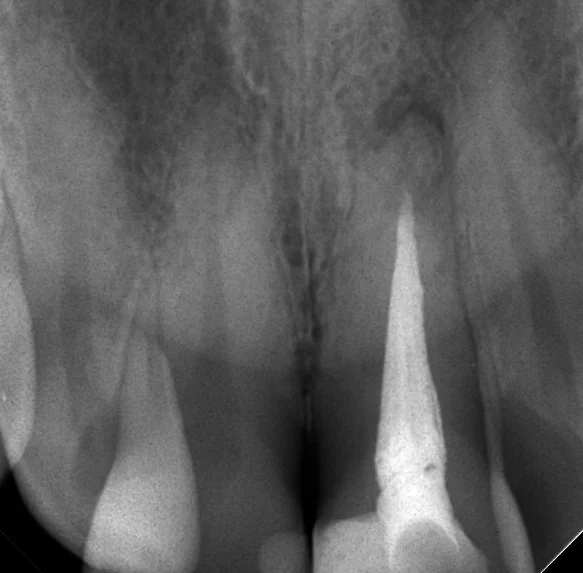

根管内が綺麗に出来たので、根管充填(最終的なお薬を詰めること)を行ったときのレントゲンがこちらです。

根の先の膿に変化はありません。

治療開始から根管充填まで治療回数は3回、治療期間は1ヵ月半くらいでした。

この膿はうちのレントゲンで確認出来るだけでも、前の院長の時代からありましたので、最低でも4~5年以上前から放置されている状態でした。

当然それだけの年月をかけてゆっくりと骨が溶かされて行っていますので、1ヵ月半程度で直ぐに骨が出来てくるという事はありません。

で、この間、口腔内を見た際に1年経過するところだったので、その経過のレントゲンを撮らせて頂きました。

その写真がこちらです。

まだ骨が治りきってはいませんが、大分骨が出来てきていますね!